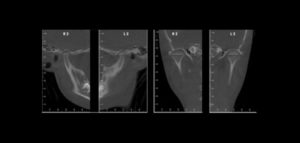

91- Anquilosis de la articulación temporomandibular como una complicación de la artritis séptica neonatal

La artritis séptica es una infección purulenta de alguna articulación, la cual se produce cuando los microorganismos invaden el espacio de alguna articulación, ya sea